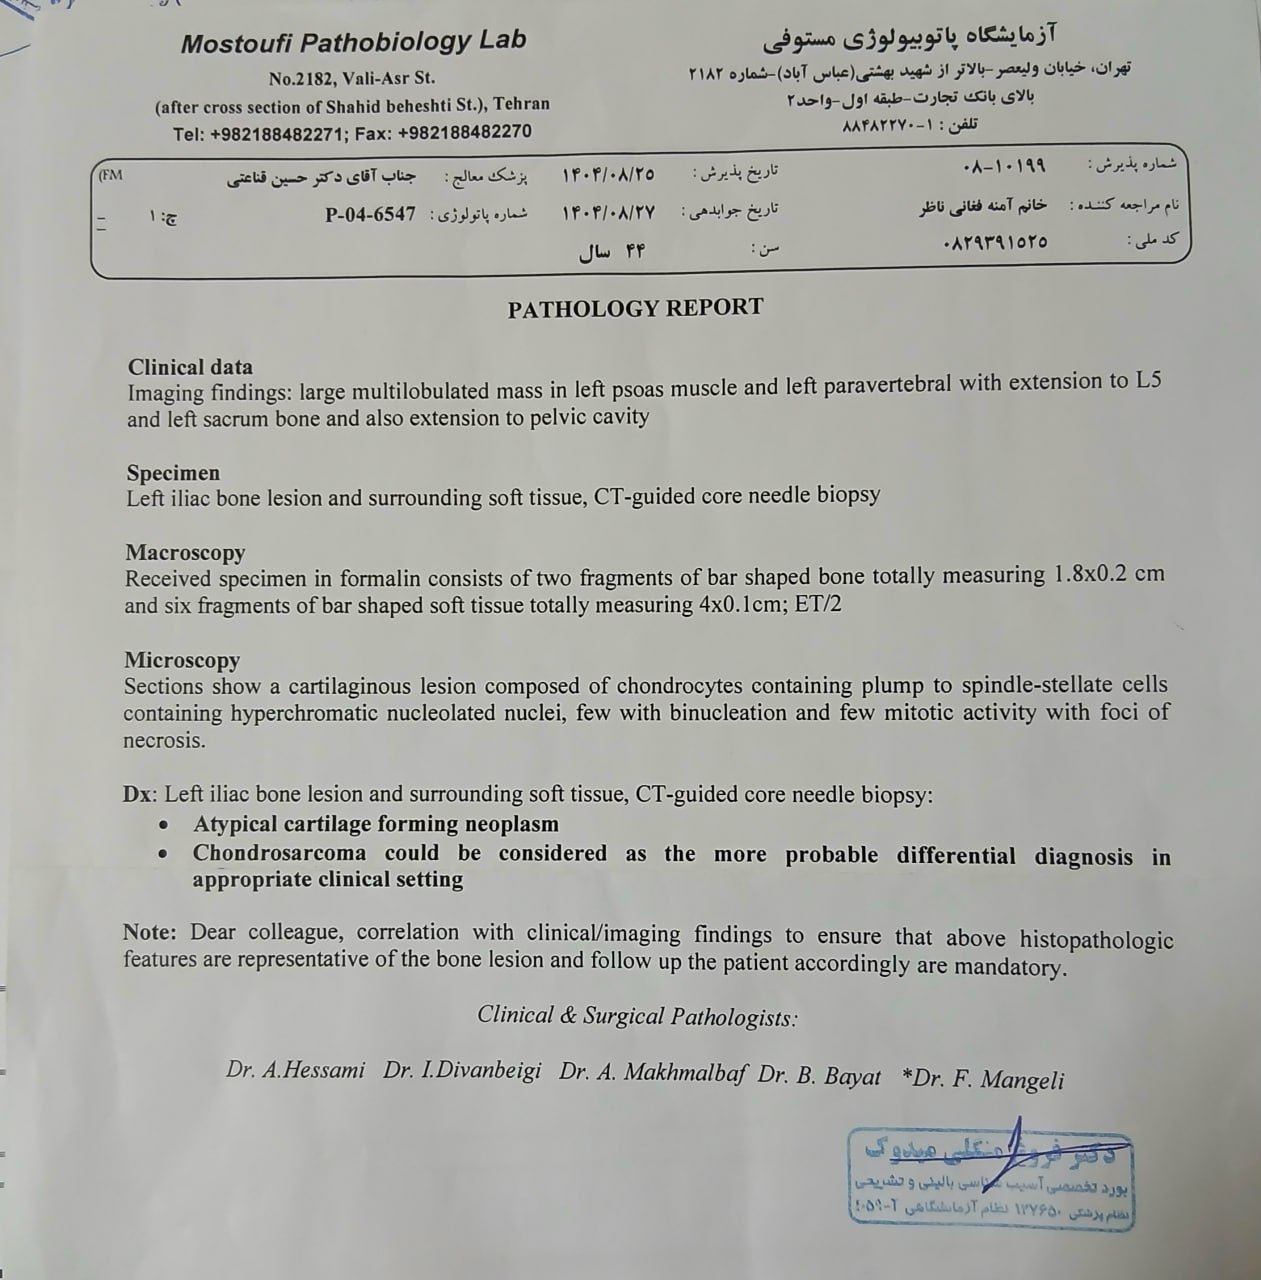

در بررسیهای تصویربرداری (MRI)،در تاریخ 24.7 ، تودهای با تشخیص کندروسارکوما همراه با DVT گزارش شده است. بیمار سابقه درد لگن داشته که شدت آن در حال حاضر نسبت به گذشته کاهش یافته است. به گفته بیمار، حجم توده در ابتدا در حدود اندازه یک تخممرغ بوده که در حال حاضر کاهش یافته است. همچنین تورم اندام تحتانی در حال حاضر نسبت به قبل کمتر شده است.

مراجعه کرده است. پس از بررسی های انجام شده در MRI انجام شده توده با درگیری مفصل ساکروایلیاک چپ و DVT؛ ابتدا تحت درمان DVT قرار گرفته است و سپس جهت پیگیری تومور رویت شده تحت بیوپسی قرار گرفته است و با تشخیص کندروسارکوما به این مرکز مراجعه کرده است و تحت کموتراپی و رادیوتراپی قرار گرفته و سایز تومور کاهش یافته است.